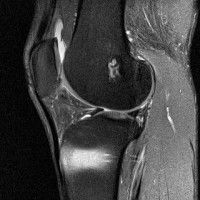

무릎 mri 간단히 봐주실 수 있으시나요 ㅠㅠ

안녕하세요 8년전 십자인대 수술하고 최근 무리한 운동에 무릎 불편감이 생겨서

mri 찍었습니다.

진단결과는 첫 찍은 병원에서 활액막염 이라는 진단을 받았습니다. 혹시 봐주실 수 있으실까요?

진단결과가 달라 혼란스럽습니다 ㅠㅠ

• 안녕하세요. 강성주 의사입니다.

올라온 MRI가 단편적이라서 정확한 진단에 어려움이 있지만 십자인대에는 큰 이상이 있지는 않은것 같으며, 무릎관절내 물이 있는 것으로 보아 활액막염의 진단이 맞을 것 같습니다.

하지만 단편적인 영상이기 때문에 촬영병원에서 정확한 판독지 등을 받으시는 것이 좋겠습니다.